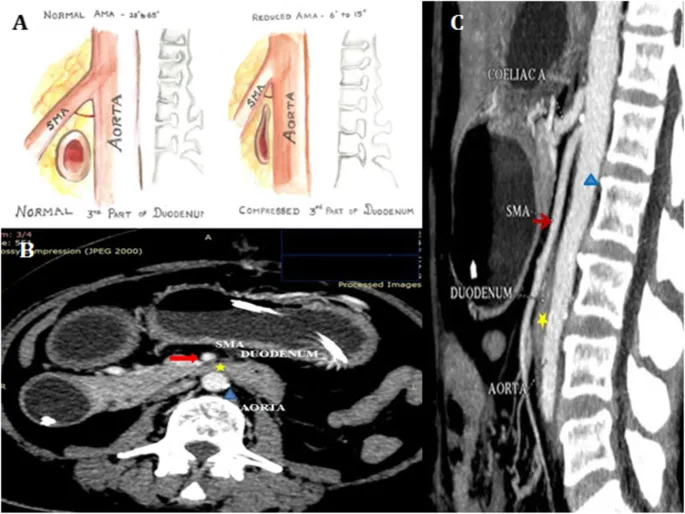

Axial Slice @ L3 - The Duodenal Squeeze

- Key Vessels: Abdominal Aorta, IVC. The Inferior Mesenteric Artery (IMA) typically originates here-the last major unpaired branch.

- The "Squeeze": The 3rd (horizontal) part of the duodenum is compressed between the Superior Mesenteric Artery (SMA) anteriorly and the Aorta posteriorly.

- Musculature: Psoas major, Quadratus lumborum, Erector spinae.

- Viscera: Lower poles of kidneys, ureters, loops of small bowel.

⭐ SMA syndrome classically presents with postprandial epigastric pain and bilious vomiting, relieved by leaning forward or lying prone, which widens the aortomesenteric angle.